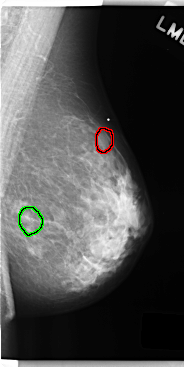

FILE: C_0247_1.LEFT_CC.OVERLAY

TOTAL_ABNORMALITIES 2

ABNORMALITY 1

LESION_TYPE MASS SHAPE ROUND MARGINS CIRCUMSCRIBED

ASSESSMENT 3

SUBTLETY 4

PATHOLOGY BENIGN

TOTAL_OUTLINES 1

BOUNDARY

ABNORMALITY 2

LESION_TYPE CALCIFICATION TYPE AMORPHOUS DISTRIBUTION CLUSTERED

ASSESSMENT 4

SUBTLETY 3